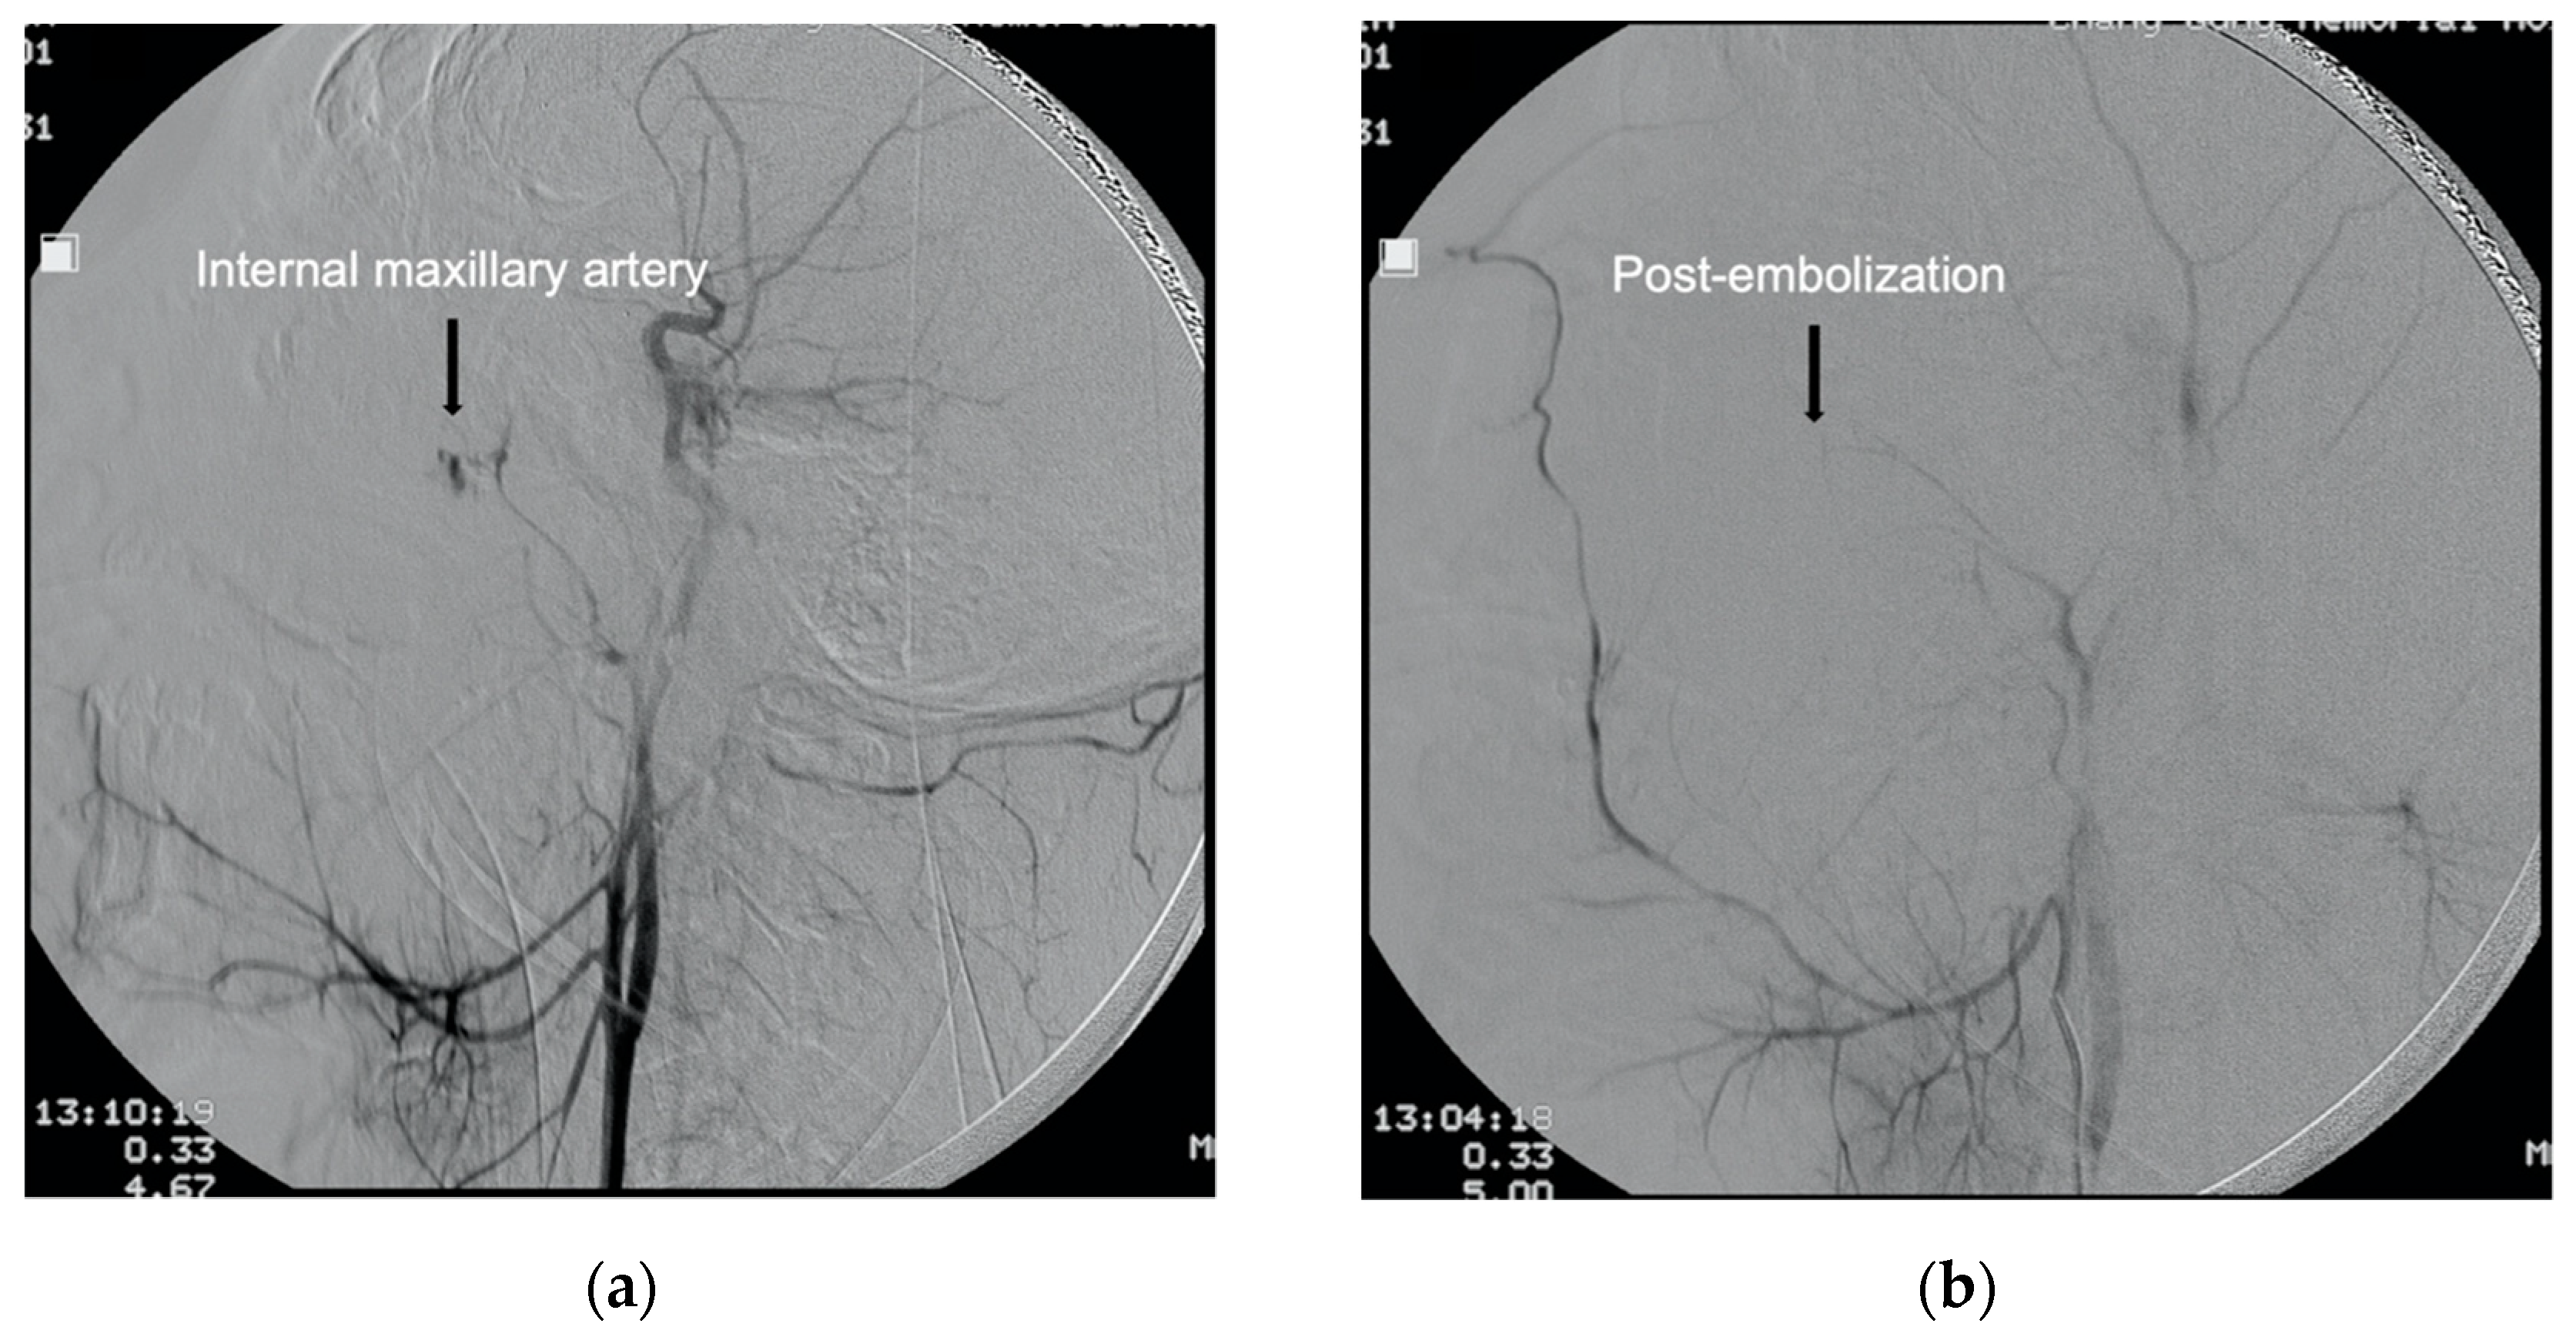

Figure 3.

Angiogram of the patient shown in Figure 2. (a) Lateral angiogram of common carotid artery shows contrast extravasation from internal maxillary artery (arrow). (b) Post gelatin foam embolization images showing hemostasis (arrow).